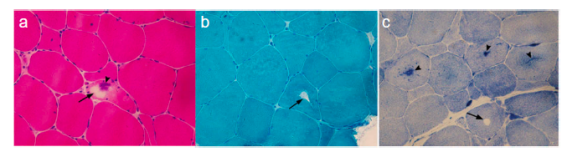

SCN4A基因突變相關的離子通道病肌肉活檢病理變現可見肌纖維中出現管聚集及空洞。